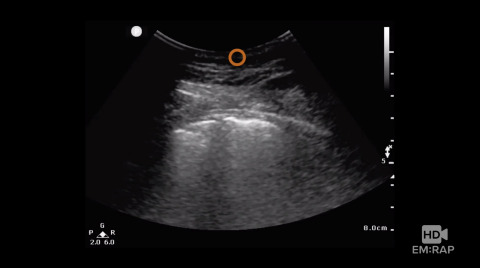

Ultrasound Findings of Viral Pneumonia and COVID

Jacob Avila reviews the ultrasound findings in viral pneumonia and the specific findings seen in COVID-19 pneumonia.